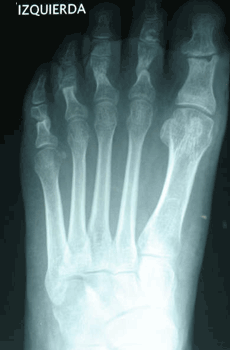

Caso 2: Hallux Valgus del Adolescente

Pie Izquierdo operado